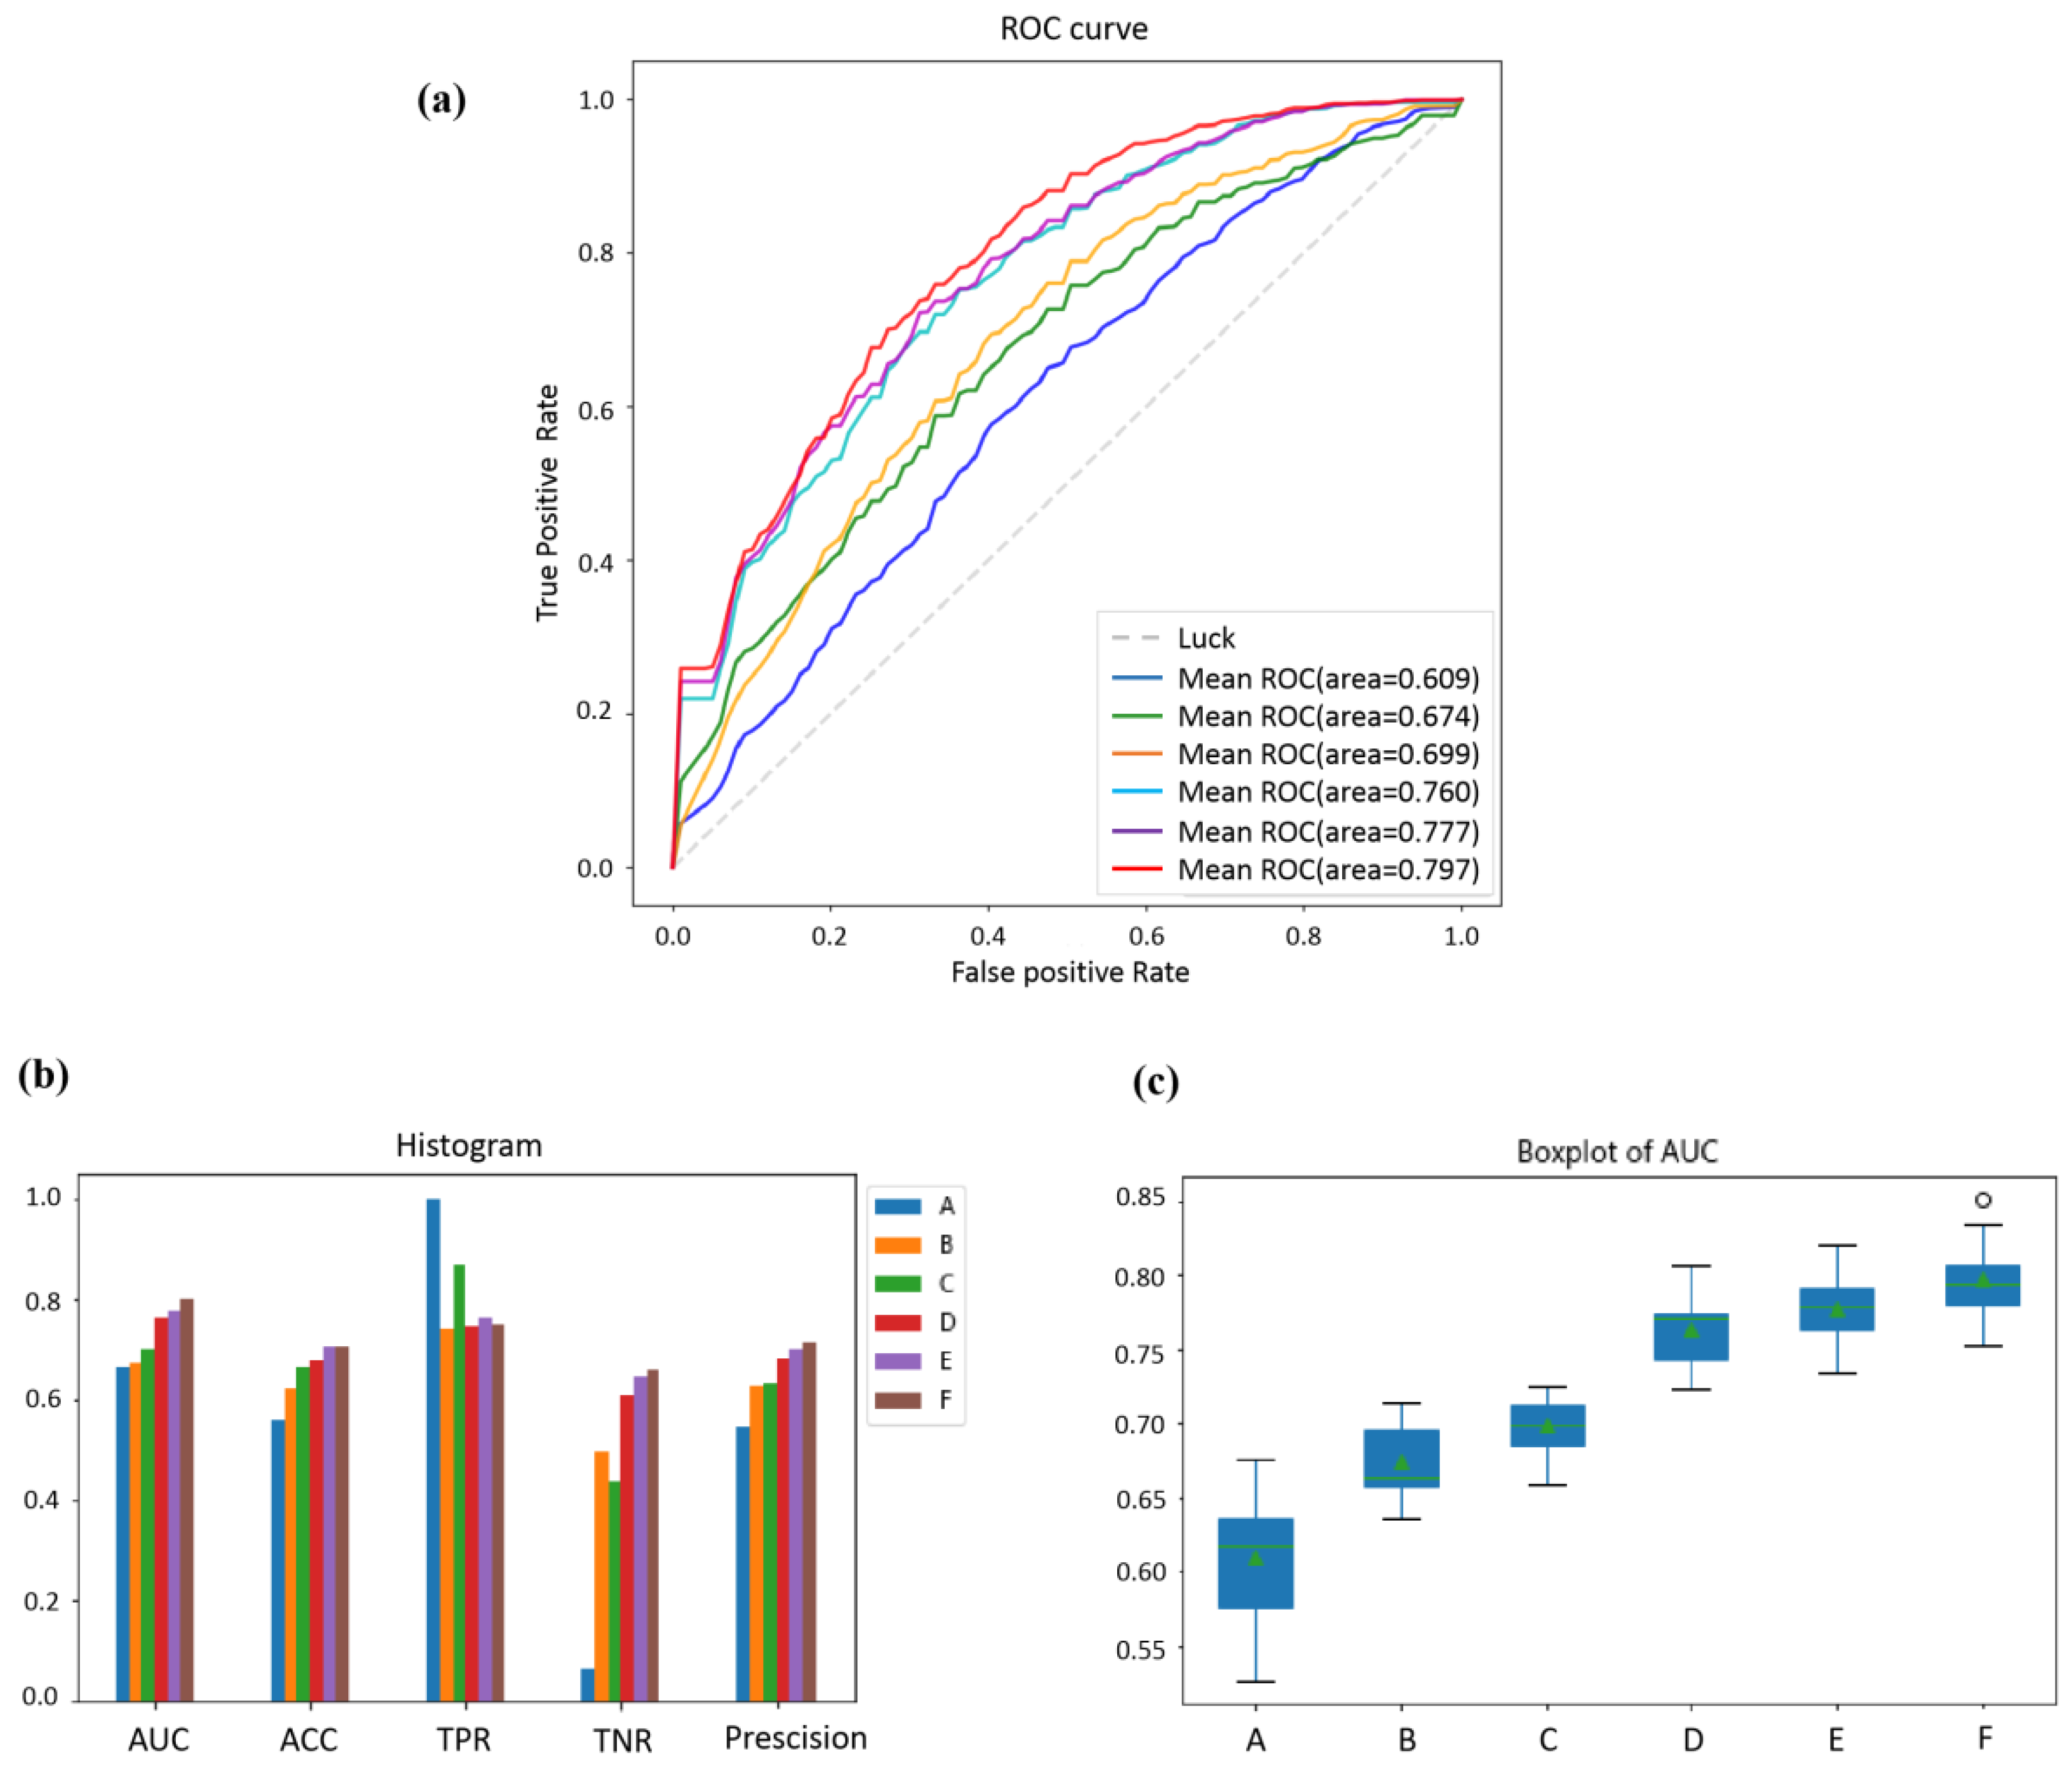

3.3. Comparisons of the Different Features of Prediction Performance

3.4. Comparisons of the Effect of Different Classifiers on Prediction Performance

| Classifier | AUC | ACC | TPR | TNR | Precision |

|---|---|---|---|---|---|

| A | 0.609 ± 0.037 | 0.582 ± 0.029 | 0.649 ± 0.047 | 0.517 ± 0.053 | 0.599 ± 0.028 |

| B | 0.674 ± 0.023 | 0.622 ± 0.027 | 0.739 ± 0.034 | 0.494 ± 0.033 | 0.625 ± 0.026 |

| C | 0.699 ± 0.019 | 0.663 ± 0.019 | 0.866 ± 0.024 | 0.435 ± 0.032 | 0.633 ± 0.017 |

| D | 0.760 ± 0.022 | 0.678 ± 0.024 | 0.765 ± 0.031 | 0.611 ± 0.026 | 0.683 ± 0.022 |

| E | 0.777 ± 0.021 | 0.704 ± 0.019 | 0.763 ± 0.033 | 0.645 ± 0.032 | 0.702 ± 0.021 |

| F | 0.797 ± 0.023 | 0.705 ± 0.018 | 0.750 ± 0.026 | 0.660 ± 0.025 | 0.711 ± 0.020 |

| Classification Method | AUC | ACC | TPR | TNR | Precision |

|---|---|---|---|---|---|

| Bayesian | 0.688 ± 0.041 | 0.620 ± 0.015 | 0.674 ± 0.015 | 0.594 ± 0.052 | 0.634 ± 0.024 |

| Logistic Regression | 0.757 ± 0.021 | 0.687 ± 0.021 | 0.749 ± 0.025 | 0.625 ± 0.031 | 0.694 ± 0.018 |

| KNN | 0.748 ± 0.017 | 0.691 ± 0.035 | 0.740 ± 0.030 | 0.650 ± 0.049 | 0.683 ± 0.027 |

| SVC | 0.732 ± 0.015 | 0.669 ± 0.047 | 0.715 ± 0.066 | 0.602 ± 0.019 | 0.687 ± 0.026 |

| Ensemble classifier (ours) | 0.797 ± 0.023 | 0.705 ± 0.018 | 0.750 ± 0.026 | 0.660 ± 0.025 | 0.711 ± 0.020 |